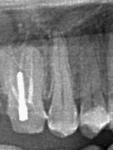

• Каналы щечного корня 1.6 зуба запломбированы в технике вертикальной конденсации горячей гуттаперчи по Шильдеру:

| Рис. 39-40 Устья запломбированных медиобуккальных и дистального каналов |

Рис. 41 Препарирование культи под м/к коронку |